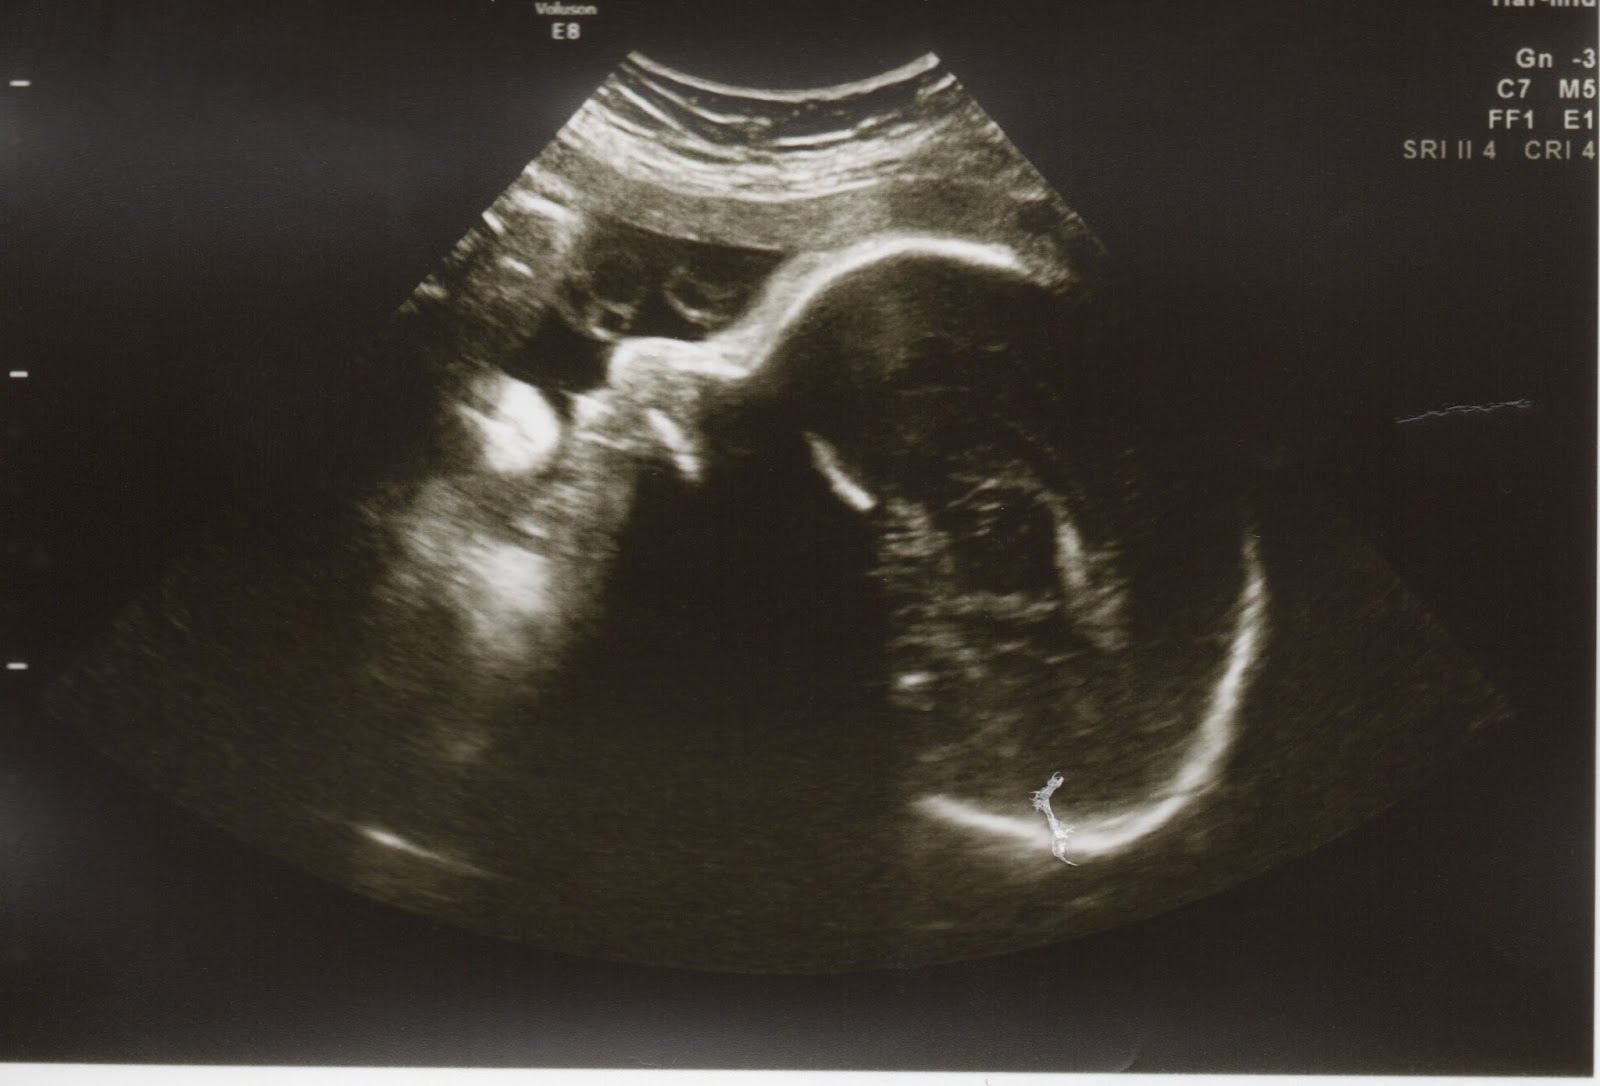

Well Nathaniel is 5 pounds 14 oz right now. He should be born around 7 pounds. This is back in line with the ultrasound 2 times ago (about 8 weeks ago).

According to this chart he will be a bit above average. Not huge like his brother! We will have to see though. He is head down (again unlike his brother) and he didn’t have his feet by his head this time! So I guess he will not be born with feet and head together! And he isn’t stuck! Everything looks good though.My OB appointment this morning also went well. I will see her in a VERY long day next week. I have to see her, then take Max to VBS, then go to a dentist appointment for Max all in one day. I think at that point I just take a nap for the rest of the day! My next appointment is Friday when I see the cardiologist and get his blessing. Hopefully I will find out the results the same day with that appointment. Well I need to get back to sewing. Max wants his backpack soon.